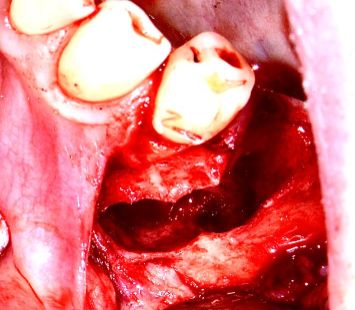

отсроченная ИМПЛАНТАЦИЯ после удаления кисты

Пациентка 65+. Радикулярная киста в области зуба 35.

Удаление зуба с заполнением остаточной полости костным графтом.

Через 6 месяцев установка имплантов VEGA 3,5х12мм.- 2 шт. и 3,5х10мм.

Протезирование через 4 месяца.